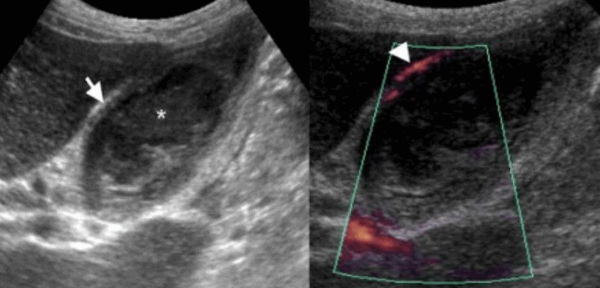

(Левый) У пациентки 67 лет с острым панкреатитом на сагиттальном УЗ срезе определяется крупное полипоидное объемное образование дна желчного пузыря, имеющее собственную сосудистую сеть.

(Правый) При МРТ в просвете желчного пузыря визуализируется дольчатое полипоидное образование, гетерогенное и гиперинтенсивное по сравнению с прилегающей печенью. Обратите внимание на угловатый конкремент в шейке желчного пузыря и отечность поджелудочной железы, вызванную острым интерстициальным отечным панкреатитом.

(Слева) На аксиальной КТ с контрастным усилением определяется распространенное круговое утолщение стенки желчного пузыря, которое проспективно было расценено как проявление ксантогранулематозного холецистита. Тем не менее, во время оперативного вмешательства обнаружился рак желчного пузыря.

(Справа) На сонограмме визуализируется объемное образование в ямке желчного пузыря и конкрементдающий акустическую тень. Образование не отделено от прилежащих отделов печени. На КТ (томограммы не продемонстрированы) была обнаружена локальная инвазия рака желчного пузыря в центральные отделы печени.